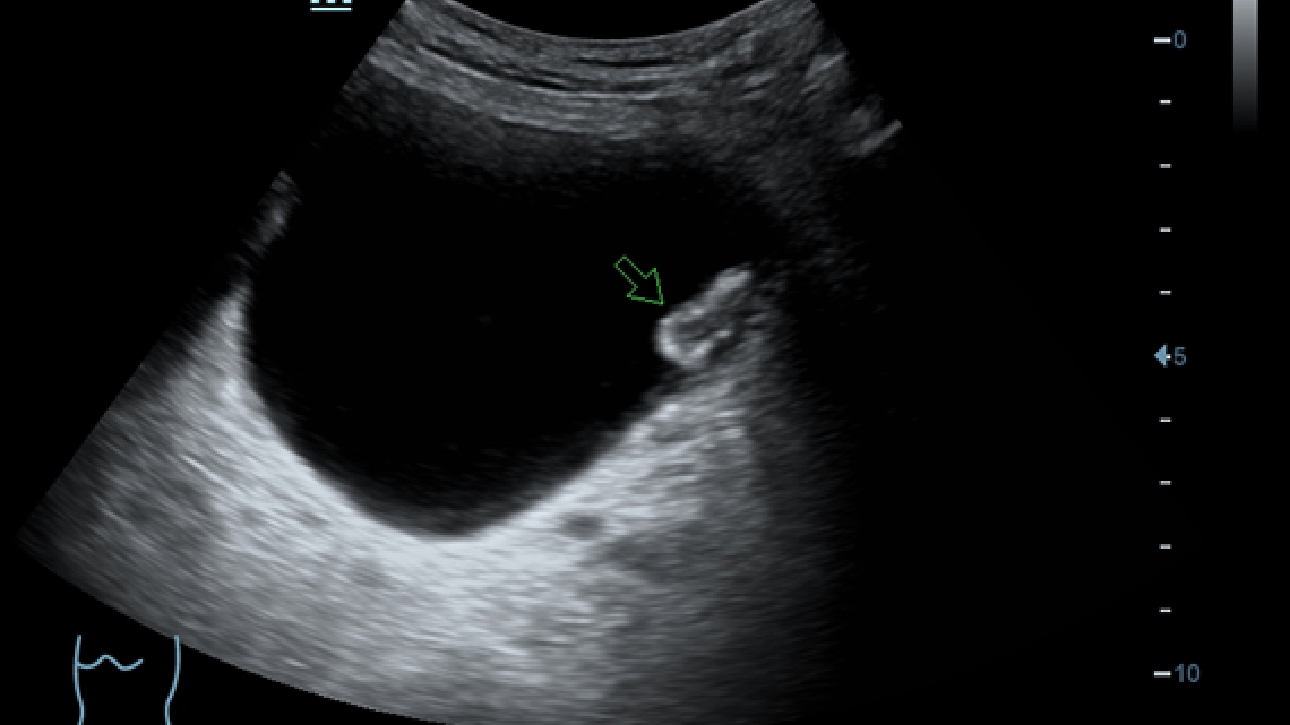

X-Insight es la soluci├│n intuitiva para una mejor visualizaci├│n.

La nueva soluci├│n de Mindray es una excelente transformaci├│n desde la continua comprensi├│n de las necesidades cl├Łnicas del usuario, combinada con la evoluci├│n de la tecnolog├Ła de los ultrasonidos m├Īs puntera. Repleto de vitalidad, con el ├║nico objetivo de visualizar el futuro y evitar los l├Łmites, el ec├│grafo DC-60Exp con X-Insight est├Ī constantemente mejorando con una escalabilidad aumentada. Como un socio personal, el equipo de ultrasonidos DC-60 Exp con X-Insight se centra en lo que verdaderamente importa, ayudando al usuario a administrar su pr├Īctica cl├Łnica con facilidad y seguridad.

Bas├Īndose en una profunda comprensi├│n de las necesidades del usuario, el sistema de ultrasonidos DC-60 Exp con X-Insight est├Ī dise?ado para ofrecer una alta eficiencia con im├Īgenes de precisi├│n, la cual se ve potenciada por una claridad inmediata, una inteligencia excepcional y benefici├Īndose de una c├│moda experiencia.